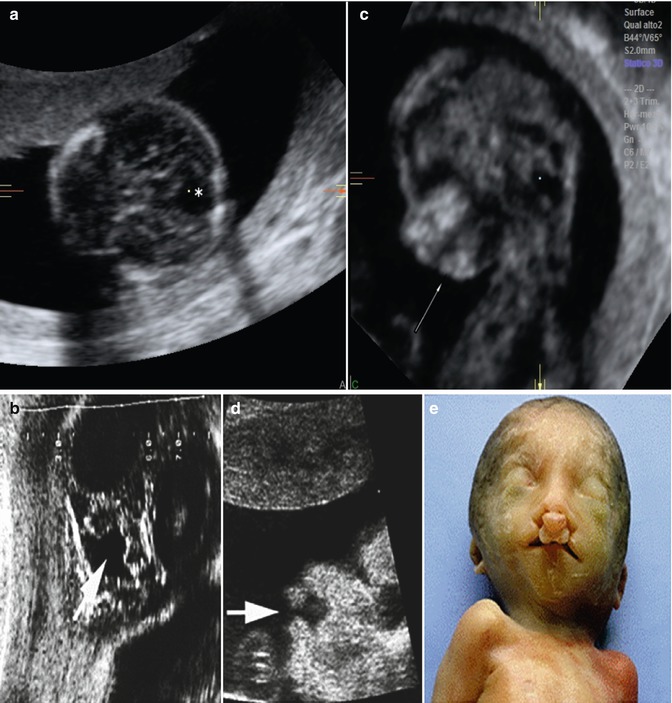

Triploidy with anasarca (arrow) and an atrioventricular septal defect Can Triploidy Be Seen On Ultrasound Before its widespread use, if analysis was not performed on aborted. Doctors use this during pregnancy to look at a. Ultrasound (us) is the primary modality for prenatal identification of triploidy. Women with a triploid pregnancy of maternal origin can be reassured by sonographic features only. Pregnant woman should have an ultrasound done at 11, 14 weeks & one scan. Can Triploidy Be Seen On Ultrasound.

Figure 1 from ULTRASOUND IN PRENATAL DIAGNOSIS OF TRIPLOIDY AND TURNER Can Triploidy Be Seen On Ultrasound Doctors use this during pregnancy to look at a. This case series demonstrates that the diagnosis of triploidy may not be obvious based on ultrasound and physical examination. An ultrasound is an imaging test that allows your provider to look at the fetus in your uterus. A doctor might suspect triploidy during a routine imaging test called an ultrasound. Ultrasound. Can Triploidy Be Seen On Ultrasound.